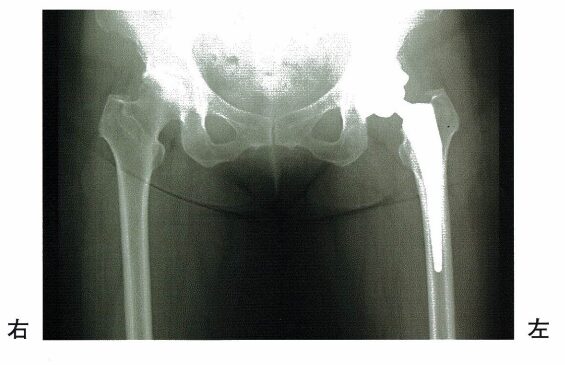

7 65歳の女性。左変形性股関節症。3年前からの左股関節痛に対して、後方進入法で人工股関節置換術を受けた。術後のX線写真を下に示す。

手術後3週までの患側下肢に対する理学療法で正しいのはどれか。

(※表引用:「人工股関節置換術のクリニカルパス」猫山宮尾病院様HPより)

・65歳の女性(左変形性股関節症)。

・3年前:左股関節痛に対して、後方進入法人工股関節置換術を受けた。

人工股関節置換術のプロトコル(計画・手順)をおさえておこう。

【人工骨頭置換術の患側脱臼肢位】

①後方アプローチ:股関節内転・内旋・過屈曲

②前方アプローチ:股関節内転・外旋・伸展